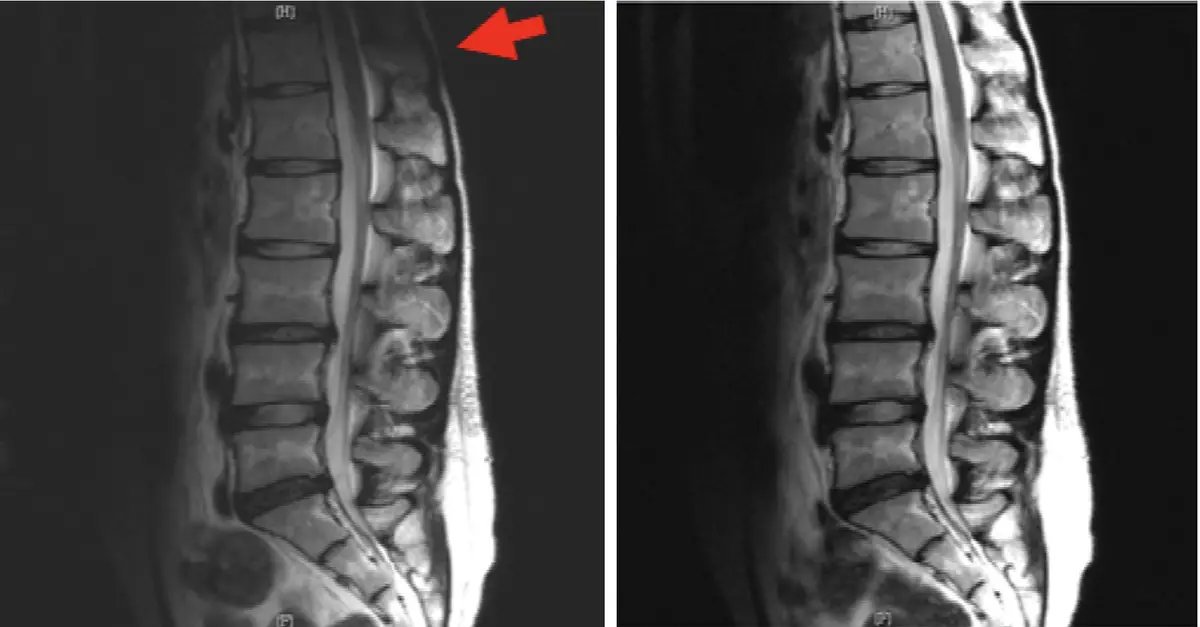

腰椎 MRI 檢查偶而發生下圖左箭號所指之低訊號現象,經改正後影像發生如下圖右。下圖左箭號所指之低訊號現象最可能的原因為何?

影像為腰椎矢狀切面 MRI 比較圖(左右並列):

左圖(有偽影):紅色大箭號(←)指向影像左上角,可見腰椎影像的上半部分(靠近頸/胸腰椎交界處)出現大片低訊號(暗區),椎體與軟組織的訊號明顯不均勻。下半部(腰骶段)影像訊號尚可,但整體影像亮度分佈不一致,呈現上段暗、下段亮的梯度分布。這種表現符合表面線圈靈敏度不均勻所造成的遮蔽偽影——線圈放置位置或覆蓋範圍不足,使上段腰椎落在線圈有效感應範圍之外,導致局部訊號顯著衰減。

右圖(改正後):改用適當的表面線圈(或正確定位後),整個腰椎矢狀面的訊號分佈明顯均勻,各節椎體、椎間盤、後縱韌帶及硬脊膜囊訊號皆可清晰顯示,上下段訊號差異消失。

本圖左右的對比清楚說明:偽影並非來自磁場本身或電流問題,而是線圈選擇或擺位不當造成的接收靈敏度不足。